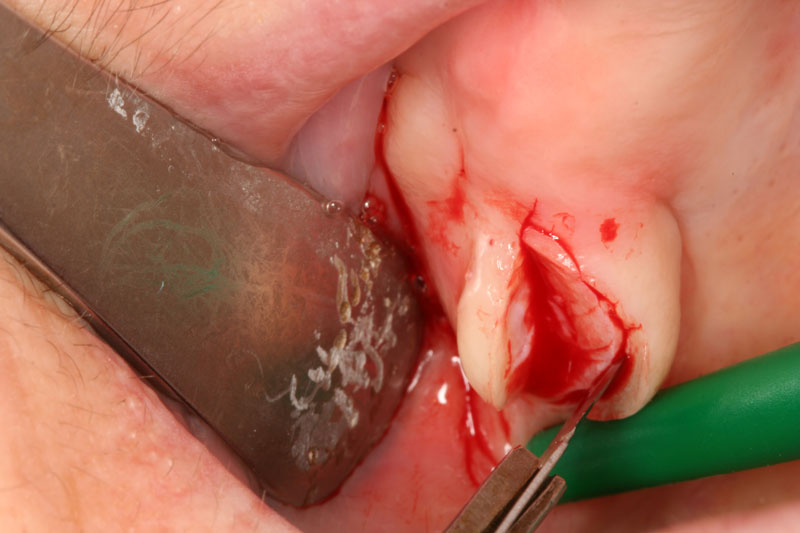

3β. αποκάλυψη εγκλείστων για ορθοδοντικούς λόγους.

- Χειρουργική αποκάλυψη εγκλείστων δοντιών για ορθοδοντικούς σκοπούς.